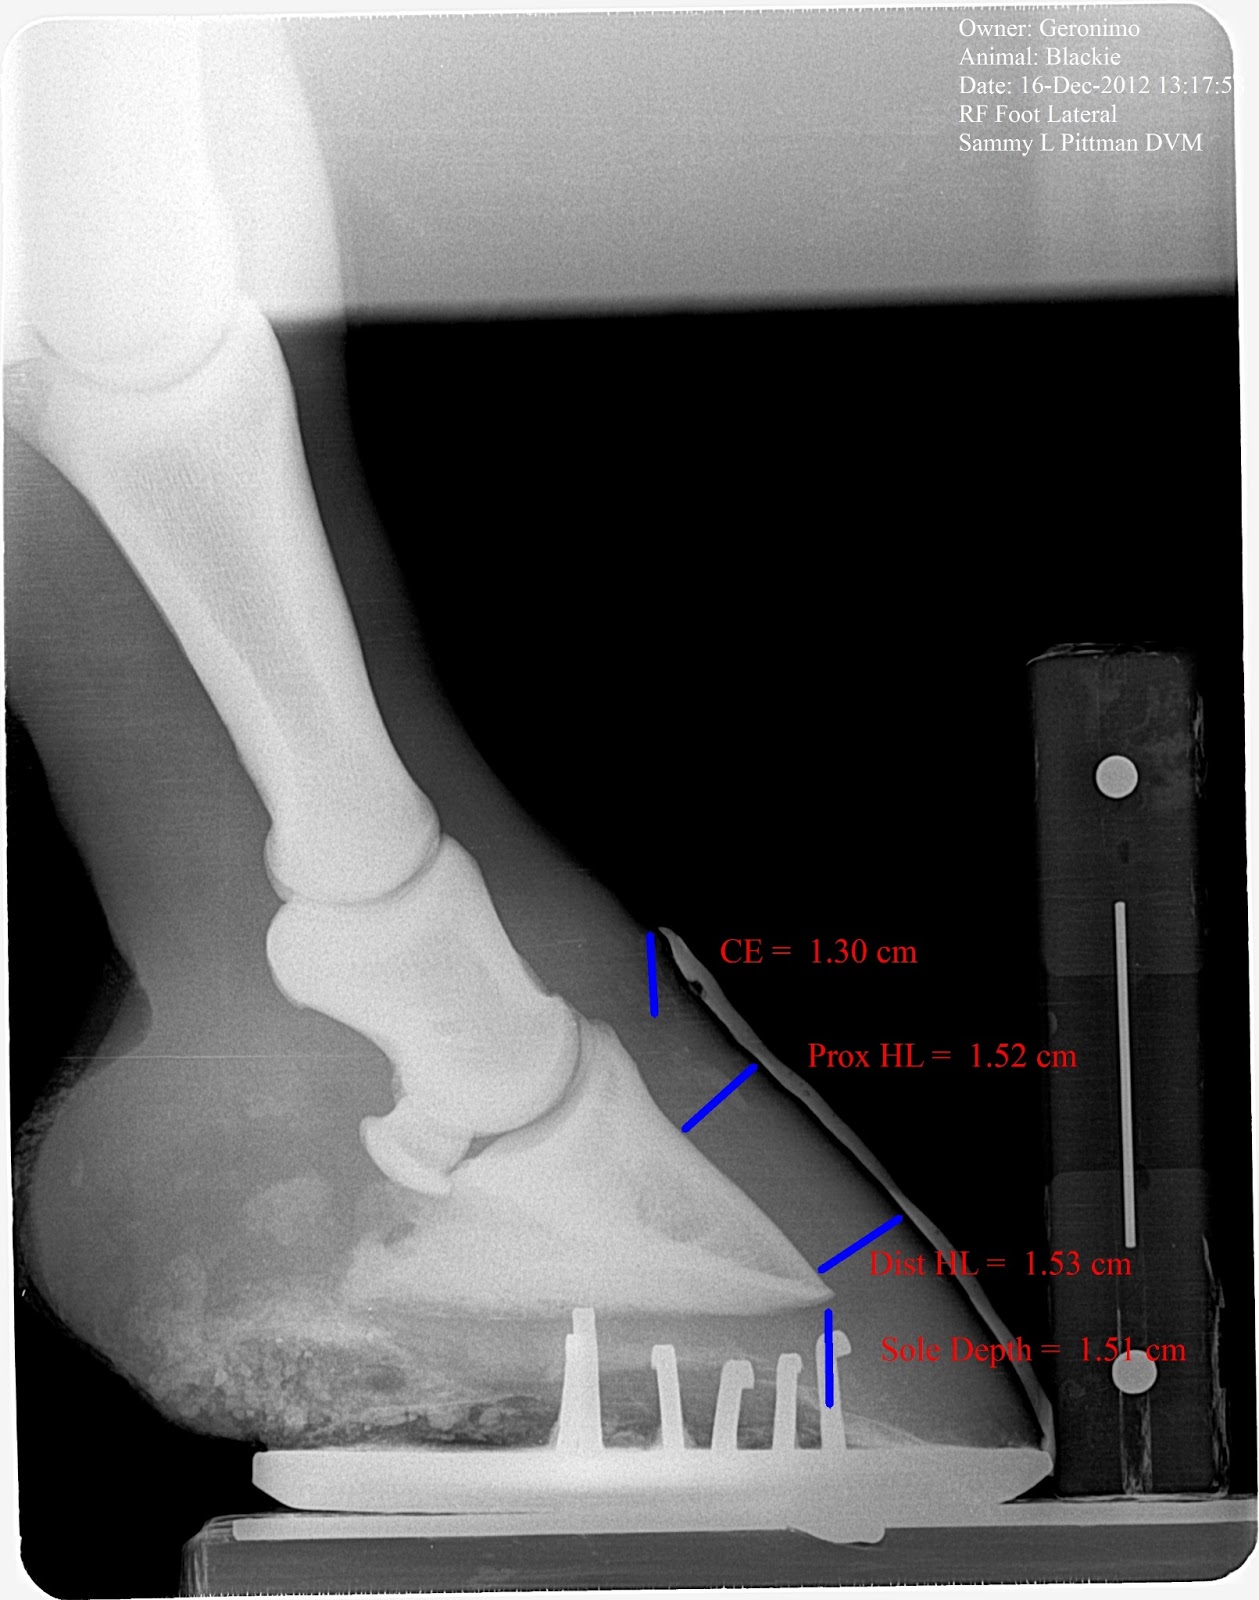

Laminitis Horse Radiographs . some horses with laminitis are shod with radiographic guidance every time to ensure proper shoe placement and. radiographs are used to assist in the diagnosis of laminitis, to monitor the progress of the disease. The hallmark clinical sign is severe lameness with bounding digital pulses. P3 rotation or sinking can result from laminar separation in the most severe cases, and it is associated with a guarded to poor prognosis. the standard radiographs that should be obtained to aid assessment of horses with laminitis are the lateromedial,. the following guidelines are not meant to be an overview of how to assess a radiograph for laminitis. the standard radiographs that should be obtained to aid assessment of horses with laminitis are the lateromedial,. causes in horses include carbohydrate overload, excess weight bearing, and endotoxemia. radiographic changes range from thickening of the region between the hoof wall and the coffin bone, change in coffin bone density, to marked rotation or.

some horses with laminitis are shod with radiographic guidance every time to ensure proper shoe placement and. the following guidelines are not meant to be an overview of how to assess a radiograph for laminitis. the standard radiographs that should be obtained to aid assessment of horses with laminitis are the lateromedial,. causes in horses include carbohydrate overload, excess weight bearing, and endotoxemia. The hallmark clinical sign is severe lameness with bounding digital pulses. the standard radiographs that should be obtained to aid assessment of horses with laminitis are the lateromedial,. P3 rotation or sinking can result from laminar separation in the most severe cases, and it is associated with a guarded to poor prognosis. radiographic changes range from thickening of the region between the hoof wall and the coffin bone, change in coffin bone density, to marked rotation or. radiographs are used to assist in the diagnosis of laminitis, to monitor the progress of the disease.